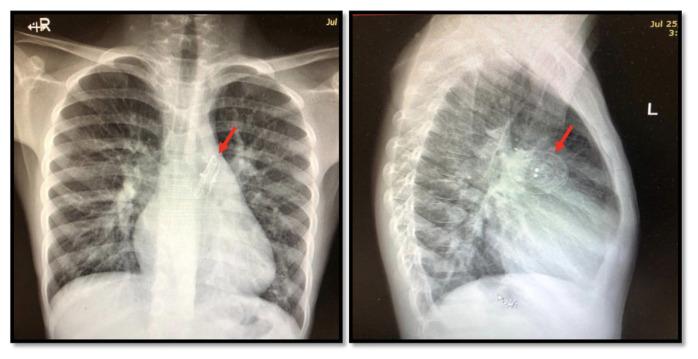

Transcatheter closure of septal defects using specialized devices is a common procedure that has a high success rate. Embolization of Atrial septal defect devices is a known complication seen at a rate of 0.5%. We report a case of late ASD device occluder embolization immediately after brain MRI with clinical consequences and intraoperative evidence of right atrial wall thermal injury. To our knowledge Atrial septal occluder (ASO) device embolization post magnetic resonance imaging (MRI) was not reported before, although theoretically possible and that's why six to eight weeks post device implantation MRI is prohibited even with current MRI compatible devices.

使用专门装置经导管闭合间隔缺损是一种成功率很高的常见手术。房间隔缺损装置的栓塞是一种已知并发症,发生率为0.5%。我们报告一例在脑部MRI检查后立即发生的晚期房间隔缺损装置封堵器栓塞病例,该病例产生了临床后果,术中发现右心房壁有热损伤迹象。据我们所知,尽管理论上有可能,但此前尚未有磁共振成像(MRI)后房间隔封堵器(ASO)装置栓塞的报道,这就是为什么即使使用目前与MRI兼容的装置,在装置植入后六至八周内仍禁止进行MRI检查。